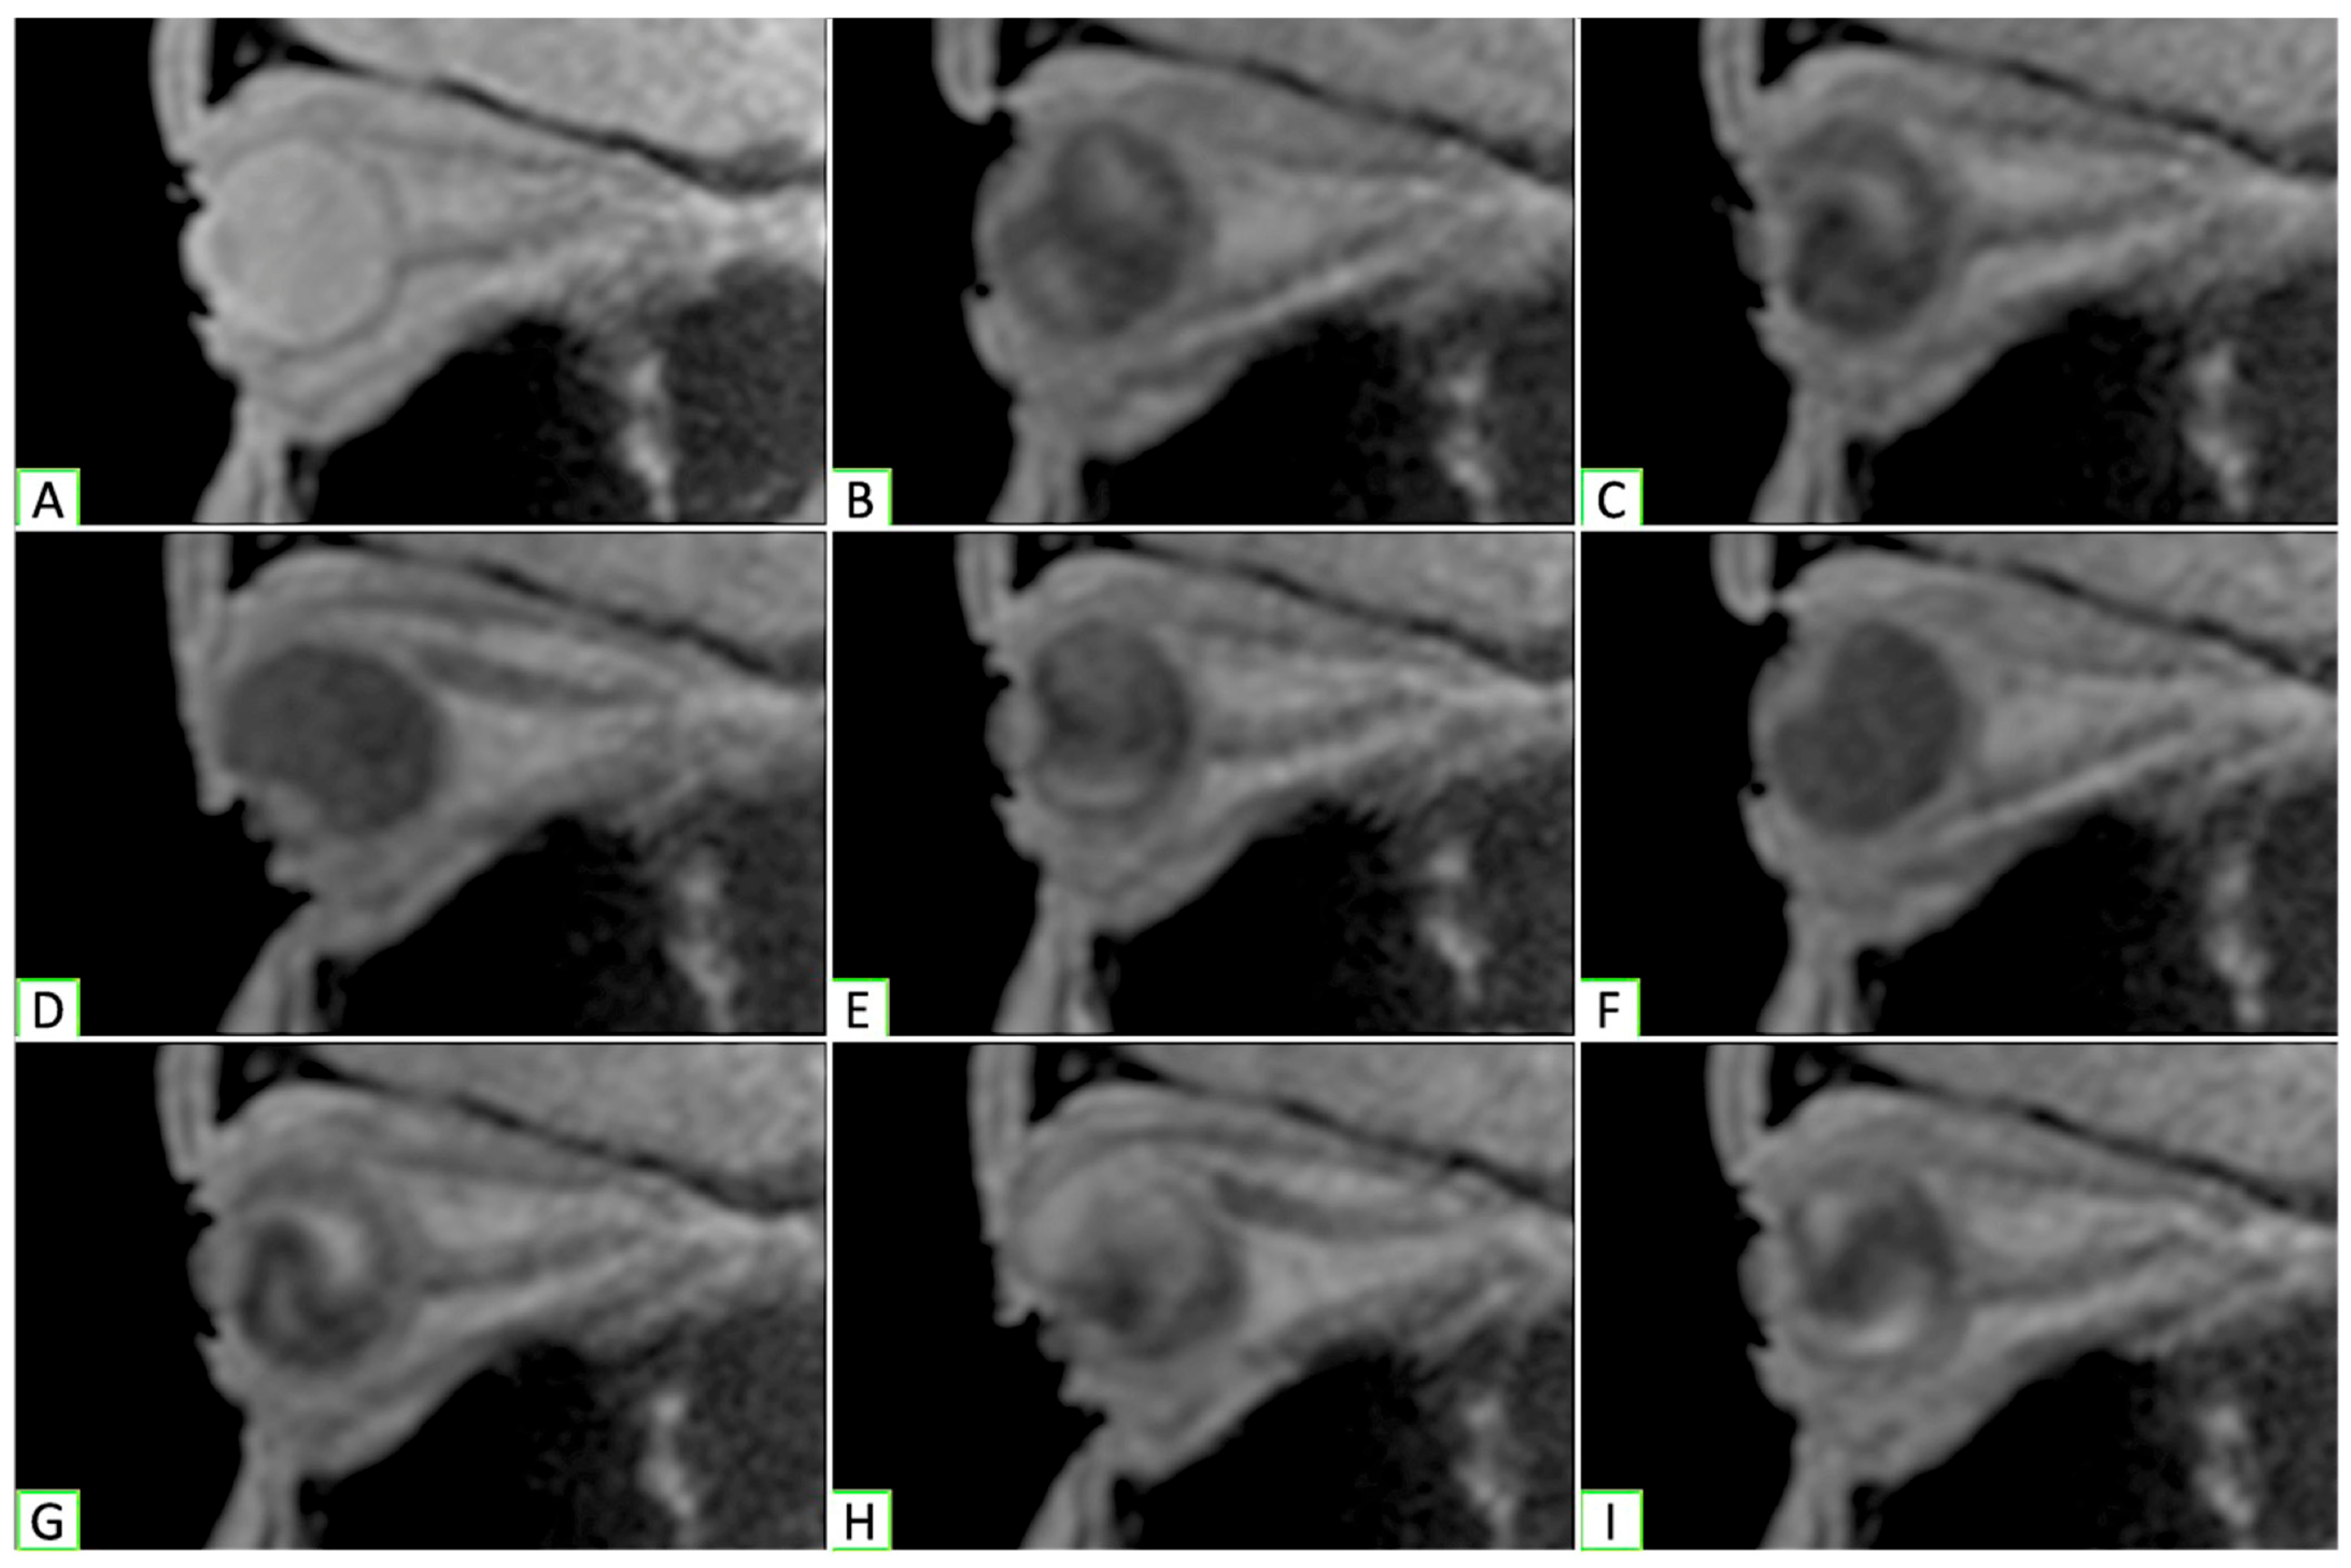

Real-Time Magnetic Resonance Imaging (rtMRI) was carried out with a 3-Tesla Siemens MAGNETOM Prisma MRI scanner (Malvern, PA, USA) augmented with 8-channel phased-array coils. Using scout images, an oblique-sagittal plane centered on the apex of the cornea and the apex of the orbit was selected to obtain rtMRI data from each orbit while the participant moved their eyes between primary, up, and downgaze. A gradient echo FLASH (fast-low angle shot) sequence was used to obtain iterative images in a single plane. A total of 90 frames were captured over a 77 s interval, which equated to two periods of oscillation per eye, providing a total of eight movements to be analyzed per eye (Figure 1).

Figure 1. Dynamic orbital MRI (Vedio S1) cuts from each position of gaze analyzed. (A,C,E,G,I) Primary; (B,F) upgaze; (D,H) downgaze.